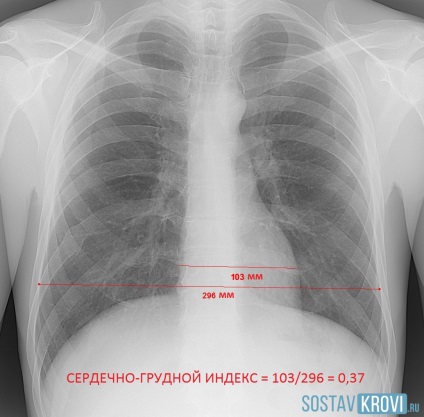

diagnosztikai módszerek kimutatására dilatáció a szív:

- Általános dilatáció a szív mint a normál mellkasi röntgenfelvétel.